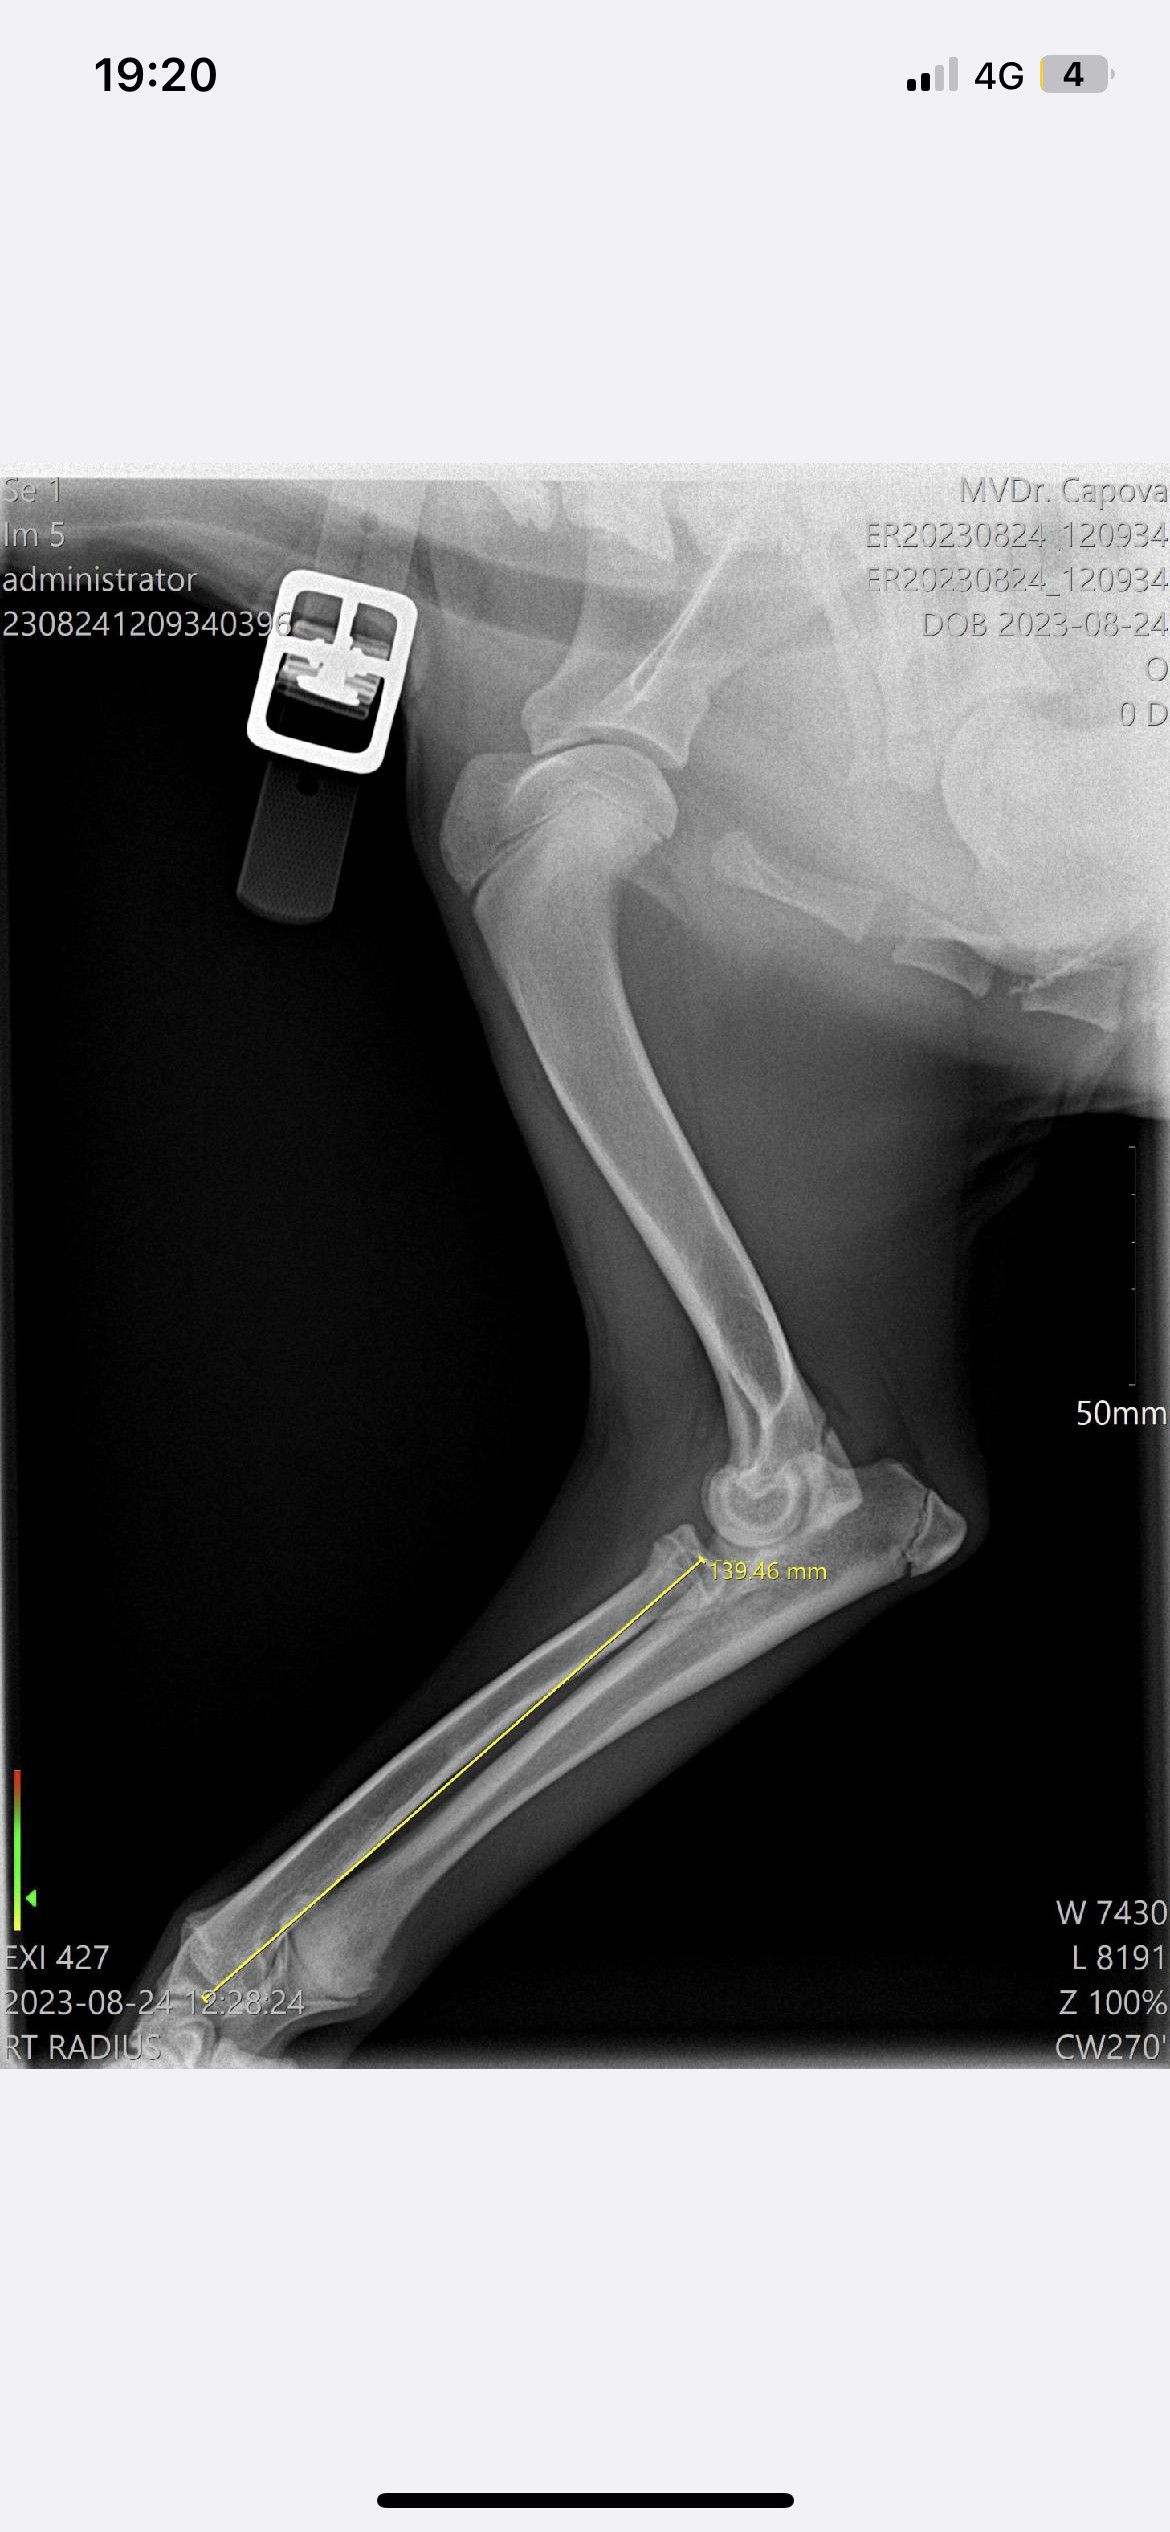

Operace a léčba pro Barlettku

Představení sbírky

Komu pomůžeme?

Na co konkrétně budou peníze z této sbírky použity?